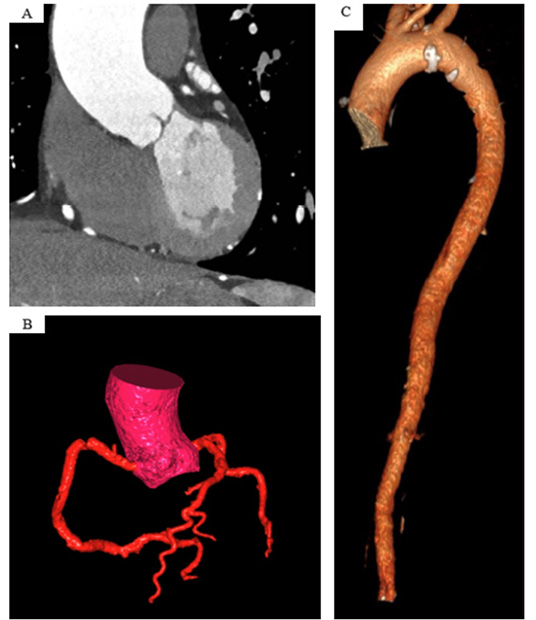

L'imagerie en coupe permet une mesure plus précise des diamètres aortiques, le caractère asymétrique de l'aorte pouvant parfois entraîner une sous-estimation de celui-ci en échocardiographie. L'IRM et le scanner peuvent être tous les deux utilisés (20). L'IRM a l'avantage de ne pas être irradiante. On utilisera des séquences SSFP (Steadystate free precession) permettant une bonne différenciation entre les compartiments liquidiens et les tissus alentours et ainsi visualiser correctement la lumière aortique. Le scanner synchronisé au rythme cardiaque est irradiant mais permet des mesures plus précises que l'IRM du fait de son excellente résolution spatiale. Il faudra utiliser le mode double oblique pour s'aligner parfaitement avec l'aorte dans tous les plans. Les mesures sont réalisées en petit axe de fond de cusp à commissure ou de fond de cusp à fond de cusp (plus grand diamètres) (Figure 4). Le scanner permet également d'étudier l'anatomie de la valve aortique et de rechercher des lésions coronaires pour les patients éligibles à une intervention (Figure 5).

Figure 6.

Évaluation en scanner d'une aorte ascendante dilatée (A), reconstruction volumétrique du réseau coronaire (B) et de l'aorte thoracique (C).